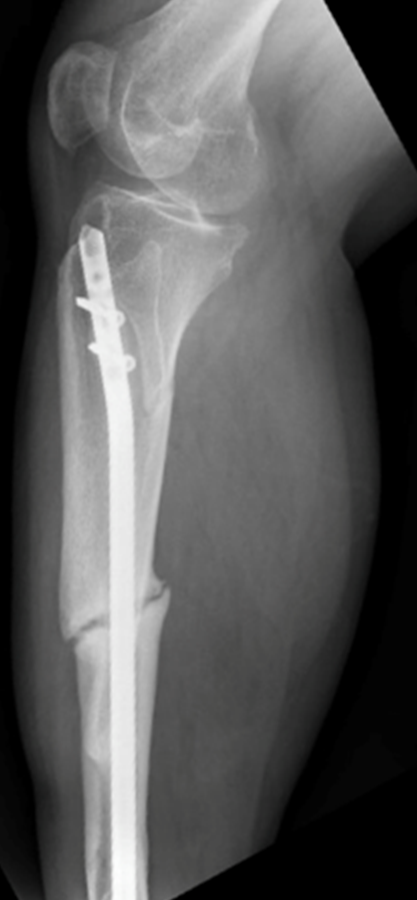

X-ray image of a nonunion fracture (Courtesy of Prof. Hannah Dailey)

Every year, nearly 10 million Americans experience a broken bone. A quarter of patients with lower leg fractures face delayed healing, and one in 10 patients will develop a nonunion, a break that requires additional major surgery to heal.

The consequences of nonunions are serious and exact a significant physical, mental, and financial toll on patients’ quality of life.